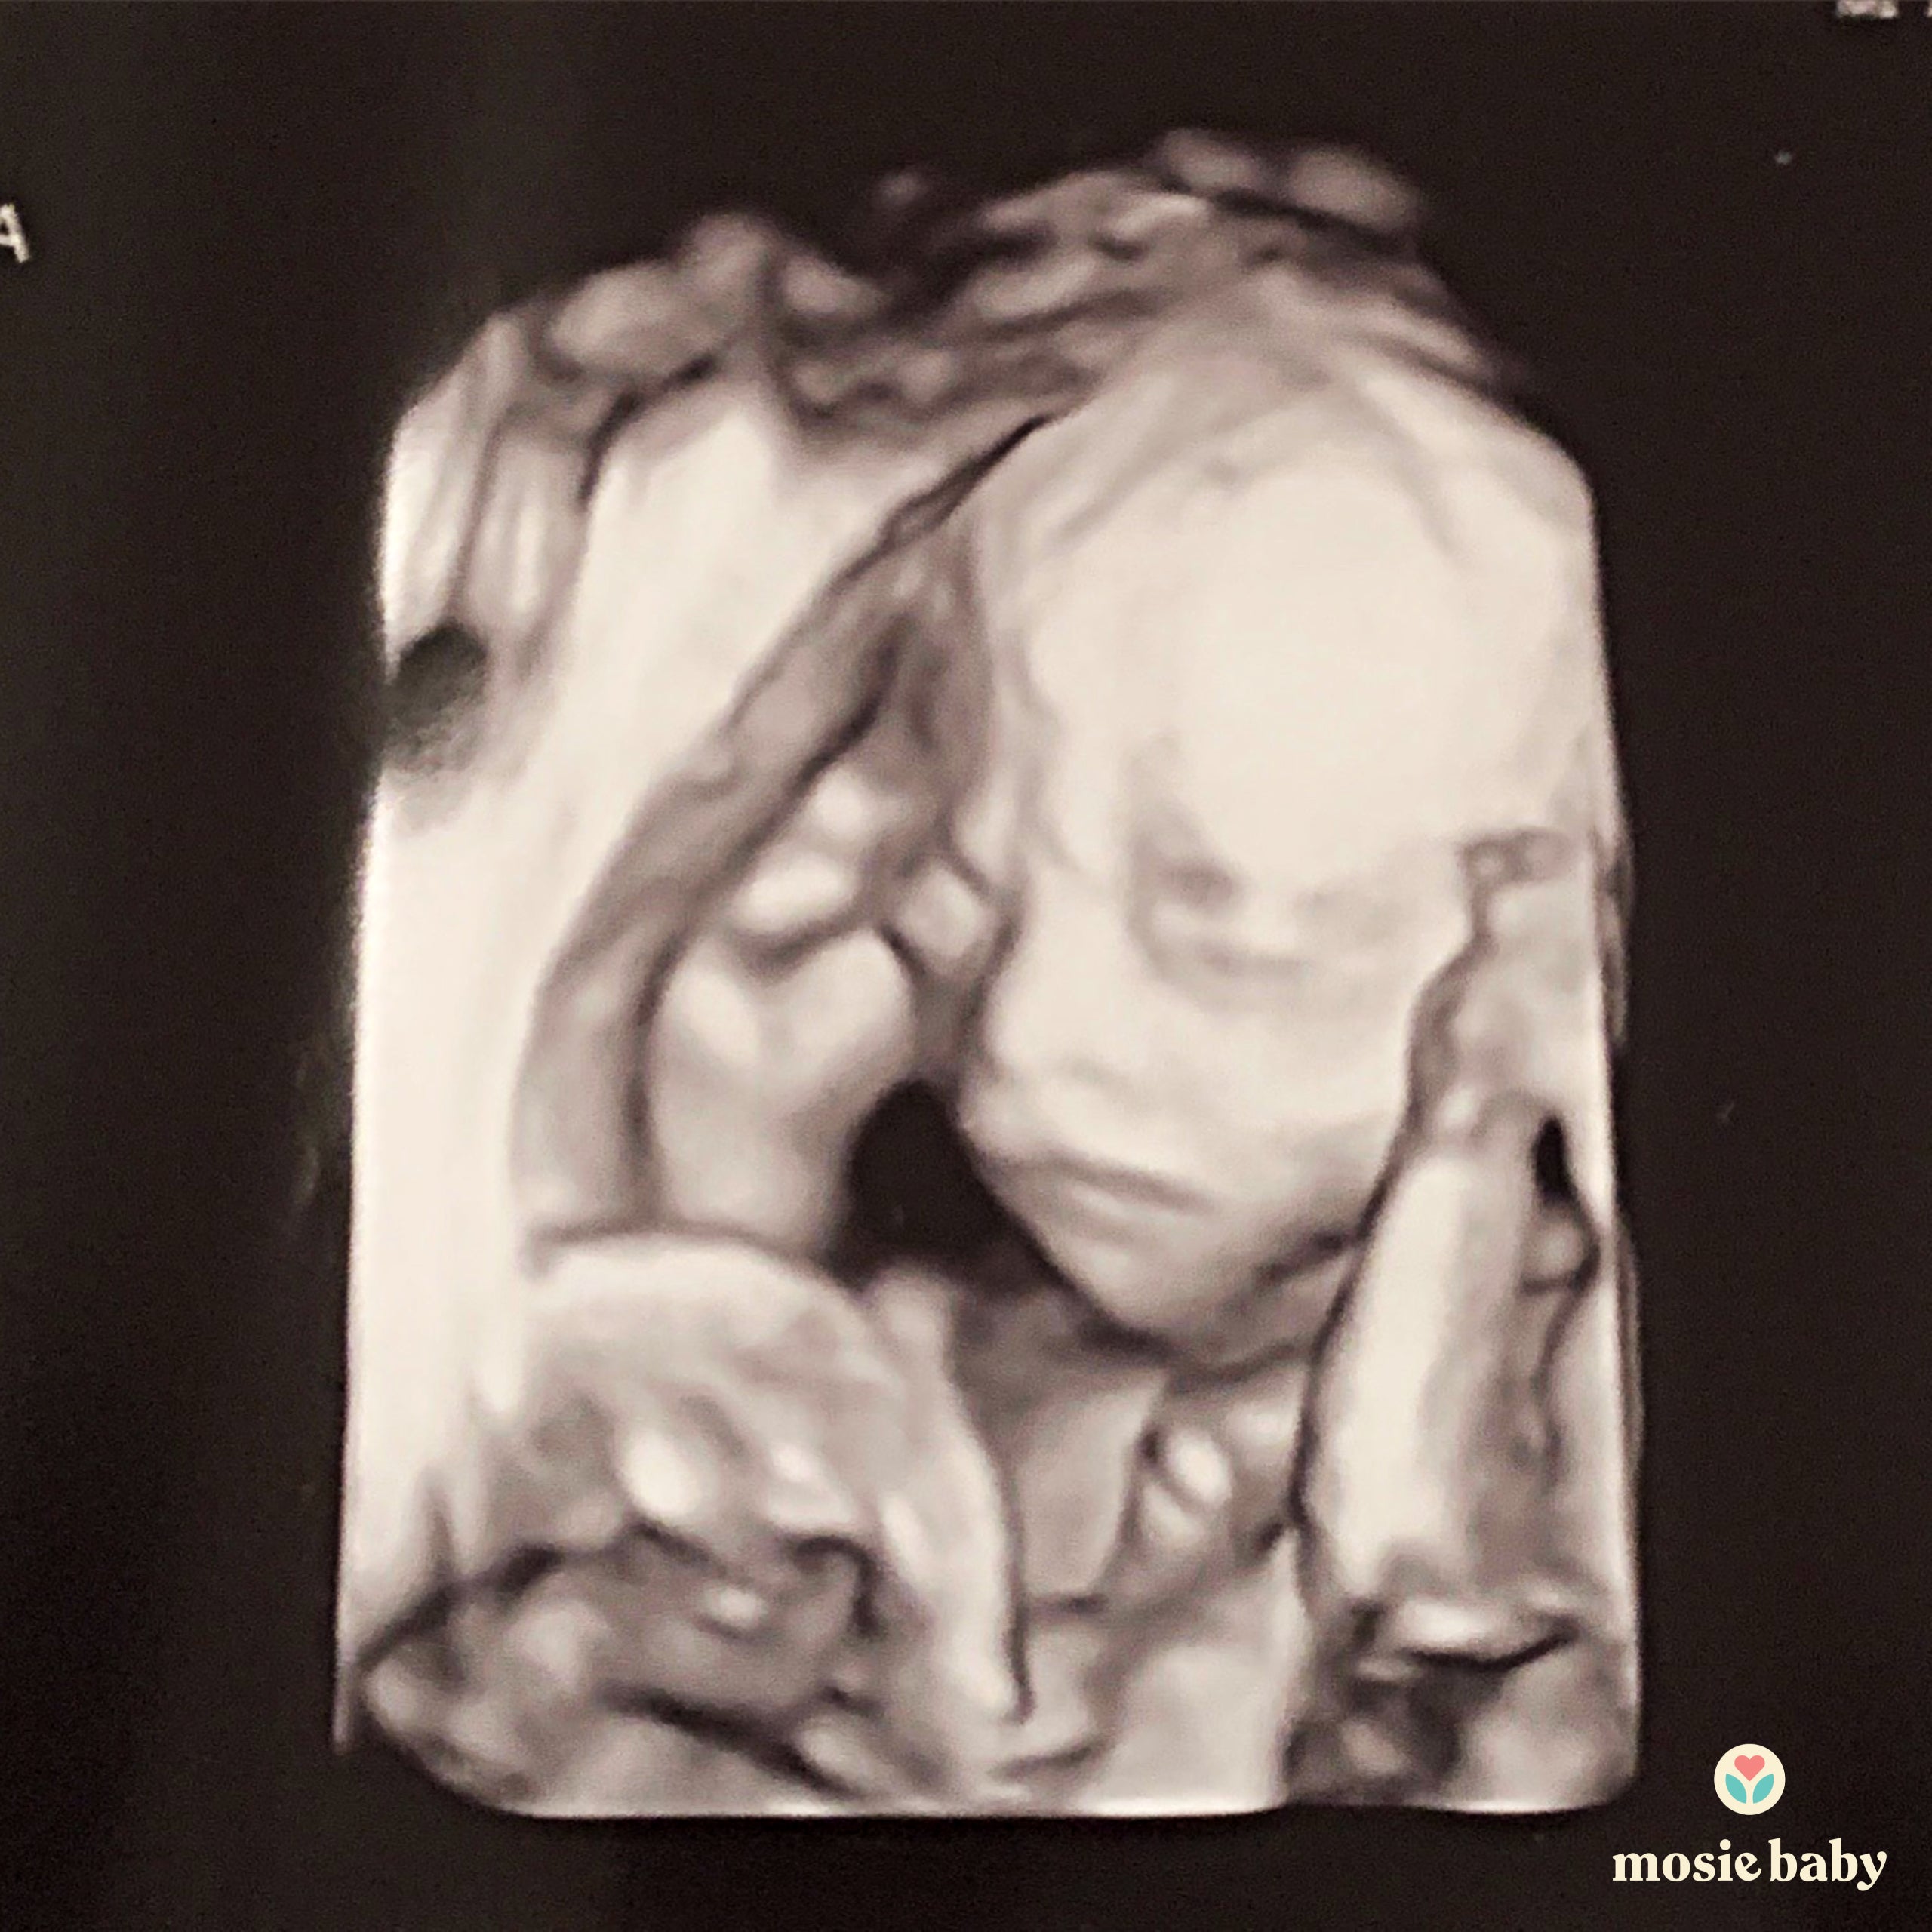

I told my husband straight away, and we were overjoyed! A few weeks later when we went for our first scan we found out we were having twins! I am now happy to report that we are almost in the third trimester and eagerly waiting for our twin girls to arrive!